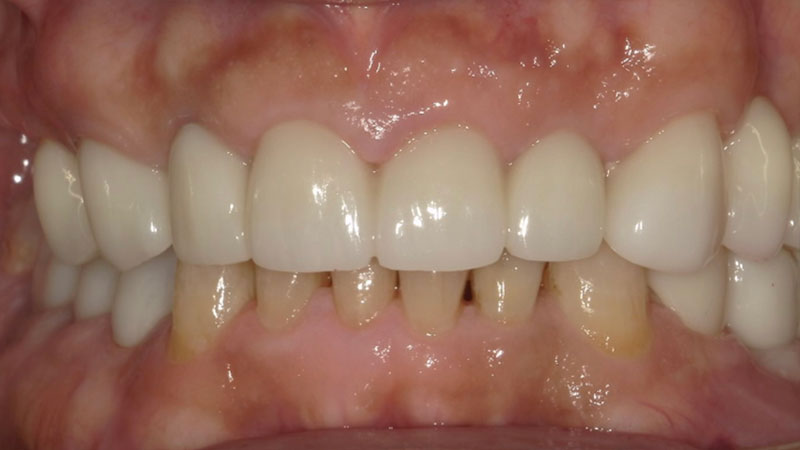

受け口の矯正

患者さんの悩みは下の前歯が出ていること、いわゆる受け口が気になるとのことでした。

非抜歯矯正を望まれたので非抜歯矯正の得意なマウスピース矯正のインビザラインをご提案いたしました。

患者さんの悩みであった前歯の見た目が改善されたこと、しっかり奥歯で噛めることでとても喜ばれていました。

| 患者様 | 40代男性 |

| 主訴 | 下の前歯が出ているのが気になる |

| 所見 | 反対咬合 |

| 治療装置 | インビザライン |

| 装置装着部位 | 全顎 |

| 治療費 | 88万円(税込) |

| 治療期間 | 約2年(約30回通院) |